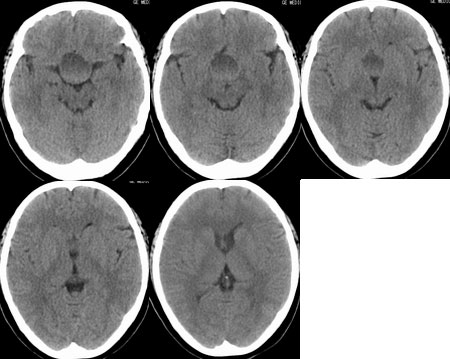

性别  女    年龄 45

阵发性头痛伴视物不清两年余

鞍区垂体窝内见一巨大类椭圆性软组织块影,前后床突受压移位、变薄,鞍底凹陷,应当能明确诊断垂体瘤。不过最好能做个mri看看视神经受累情况

蝶鞍内圆形密度不均匀,包膜完整肿块影,前床突与鞍底变薄.

意见:垂体大腺瘤.

本病例单凭ct检查是很难定位准确的,是鞍上病变侵犯鞍内、还是鞍内病变向鞍上生长?

1、如果鞍内肿瘤突破鞍隔,向鞍上生长,考虑垂体腺瘤,其典型表现是肿瘤呈"8"字征。

2、如果是鞍上肿瘤侵犯鞍内,要考虑鞍区脑膜瘤、生殖细胞瘤、实性颅咽管瘤(多为囊性、少数也可实性)、转移瘤、垂体柄胶质细胞瘤。